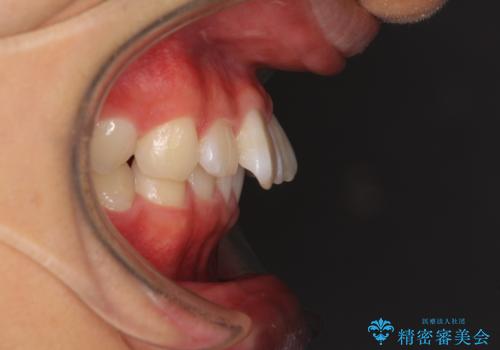

深い咬み合わせとデコボコ ワイヤー矯正で短期治療

- 前歯のデコボコを改善したいとのことで来院された患者様です。

インビザラインでの治療も可能でしたが、深い咬み合わせと奥歯の咬み合わせを改善するにあたり、ワイヤー矯正の方が治療期間を短縮できると判断し、ワイヤー矯正をお勧めしました。